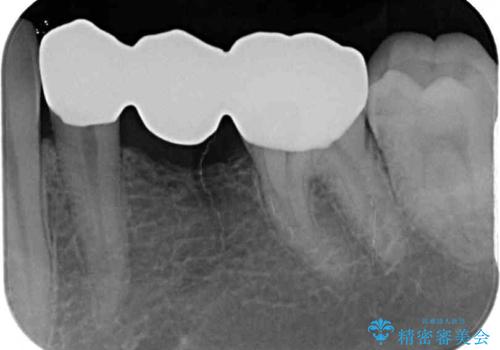

オールセラミックブリッジとしたことで、審美的かつ外れにくい補綴治療を行うことができました。